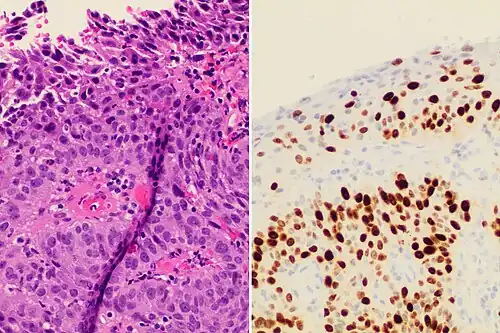

Histopathologic image (H&E stain) of carcinoma in situ (also called CIN3), stage 0: The normal architecture of stratified squamous epithelium is replaced by irregular cells that extend throughout its full thickness. Normal columnar epithelium is also seen.

Cervical intraepithelial neoplasia (CIN) means the development of abnormal cells on the surface of the cervix. HPV infections cause CIN, but in most cases, it is resolved by the immune system. However, a small percentage of people might develop a more serious CIN, which, if left untreated, can develop into cervical cancer.[66][67] CIN is often diagnosed during routine Pap smear examination or colposcopy.[67]

The naming and histologic classification of cervical carcinoma precursor lesions has changed many times over the 20th century. The World Health Organization classification system was descriptive of the lesions, naming them mild, moderate, or severe dysplasia or carcinoma in situ (CIS).[68][69] The term cervical intraepithelial neoplasia (CIN) was developed to place emphasis on the spectrum of abnormality in these lesions and to help standardize treatment.[69] For premalignant dysplastic changes, cervical intraepithelial neoplasia grading (CIN 1–3) is used. It classifies mild dysplasia as CIN1, moderate dysplasia as CIN2, and severe dysplasia and CIS as CIN3.[70] More recently, CIN2 and CIN3 have been combined into CIN2/3. These results are what a pathologist might report from a biopsy.